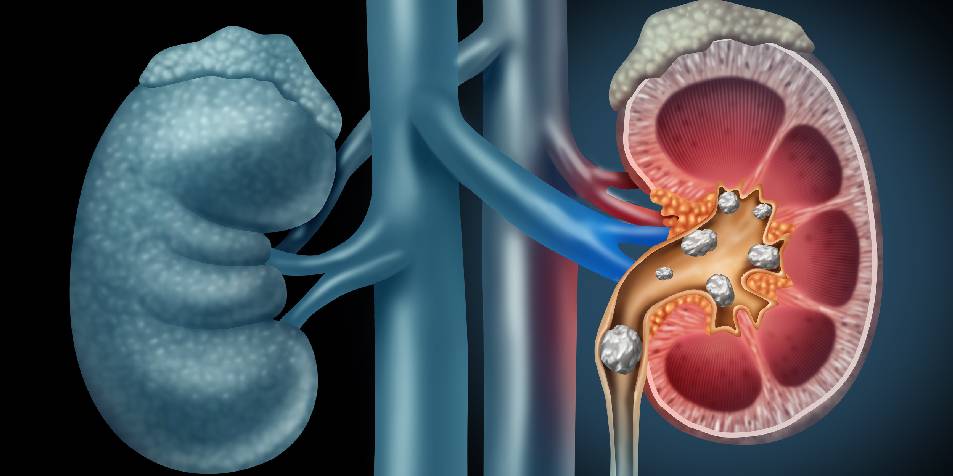

Los Cálculos renales también llamados Litiasis Renal (LR), son sólidos de tamaño pequeño que precipitan en el sistema urinario debido a algún desorden metabólico. La composición de los mismos es, en algunos casos, el único indicio para encontrar el origen de ese desorden, de aquí la importancia de realizar estudios que permitan esclarecer las fases que lo componen.

Cuando en la orina encontramos altas cantidades de ciertas sustancias que generan la formación de cristales durante semanas o meses se puede dar origen a los cálculos.

Los síntomas de la litiasis renal se verán afectados por la ubicación, tamaño y composición de los cálculos dentro del sistema urinario del paciente. Para algunos casos este padecimiento incluso será poco sintomático.

Es posible que los síntomas se manifiesten cuando el cálculo descienda por el tubo (uréteres) a mediante los cuales la orina se vacía hacia su vejiga. Al suceder esto, el cálculo puede obstruir el correcto flujo de orina desde el riñón. Un paciente puede desarrollo más de un cálculo a la vez.